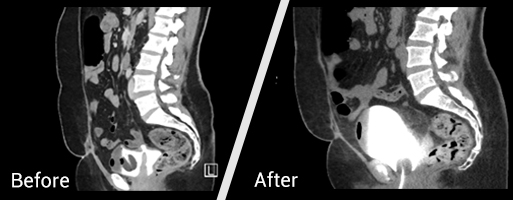

x-ray before and after Bladde​​r Fistula

A medical team in the Department ‎of Urology Surgery at King ‎Abdulaziz Medical City ‎‏-‏‎ Riyadh ‎has succeeded in performing a ‎fistula repair operation between the ‎vagina and the bladder for a Saudi ‎woman who had a previous ‎hysterectomy.‎

Then, the medical team performed ‎the fistula repair operation by ‎means of laparoscopic, in order to ‎avoid opening the abdomen.‎

Dr. Al-Sari stated that the ‎operation was successful, and the ‎patient left King Abdulaziz ‎Medical City in good health two ‎days after the operation, with a ‎urinary catheter in place for three ‎weeks, after which it was ‎confirmed that the fistula had ‎healed.‎